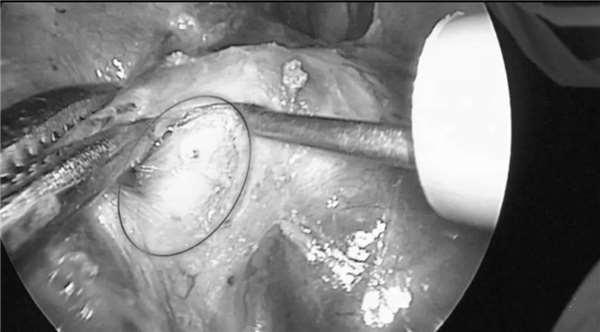

儘管在手術前,山高設想了每一個可能發生的意外情況,但是,他最擔心的事還是發生了,波琦的右肺下半葉組織沾黏在一起,擋住了動脈和靜脈。

憑著一萬台手術積累的經驗和勇氣,他沉住氣,不斷提醒手術室的人,也包括他自己:「不要慌,慢慢來...」,器具在波琦的肺泡叢林中艱難游弋,一遍遍反覆觀察、尋找,終於他們找到了那根藏起來的肺動脈。

山高把動脈結紮,然後小心地剪斷了它。